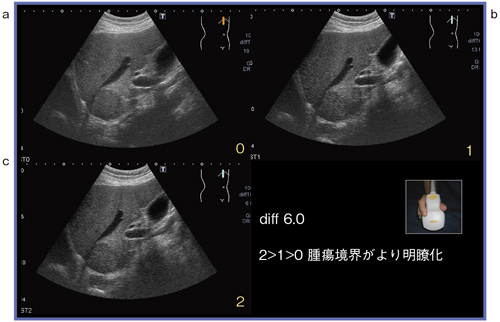

●症例4:S1転移性肝腫瘍(80歳代,男性)

S1に大腸がんの転移性腫瘍(35mm)を認める。図10のBモード画像右下の数字はBeam Enhance Technologyの適用レベルを示す。0(適用なし)〜4の5段階を選択可能である。レベル3,4ではフレームレートが下がる傾向がある。図10は,PVT-674BT/differential6.0のコンベックスプローブによるBeam Enhance Technologyである。適用なし(a)に比べてレベル1(b)と2(c)では,腫瘍の境界がより明瞭に描出され,輪郭不整像を示していることがわかる。また,腫瘍より深部の構造物もより明瞭に描出されている。differential8.0では,適用なし(a)に比べて,レベル2(b)では腫瘍の認識が容易である。明らかな違いを認識することができる(図11)。

図10 症例4:S1転移性肝腫瘍のBeam Enhance Technologyのレベルによる画像比較